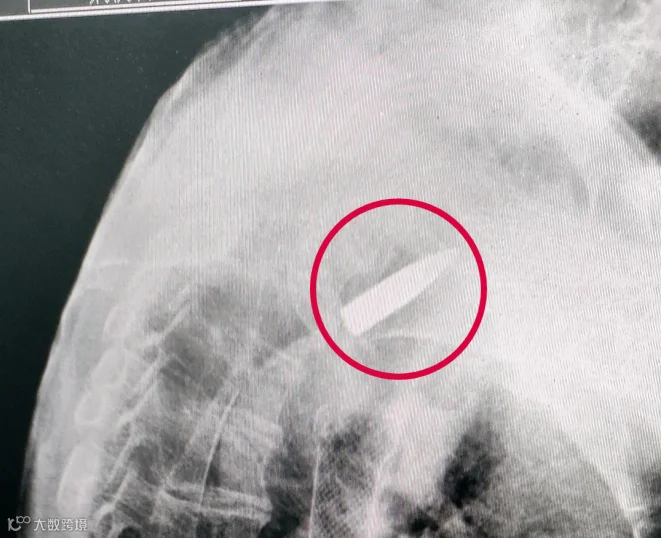

CT拍出来

医生们都吓了一跳

罗锦文的右肩里

竟然有一颗子弹

这颗“长”在他身体里70多年的子弹

是对那段历史的见证

考虑到这枚子弹对日常生活影响不大

经医院和家属商议

决定保持原状

不进行取出